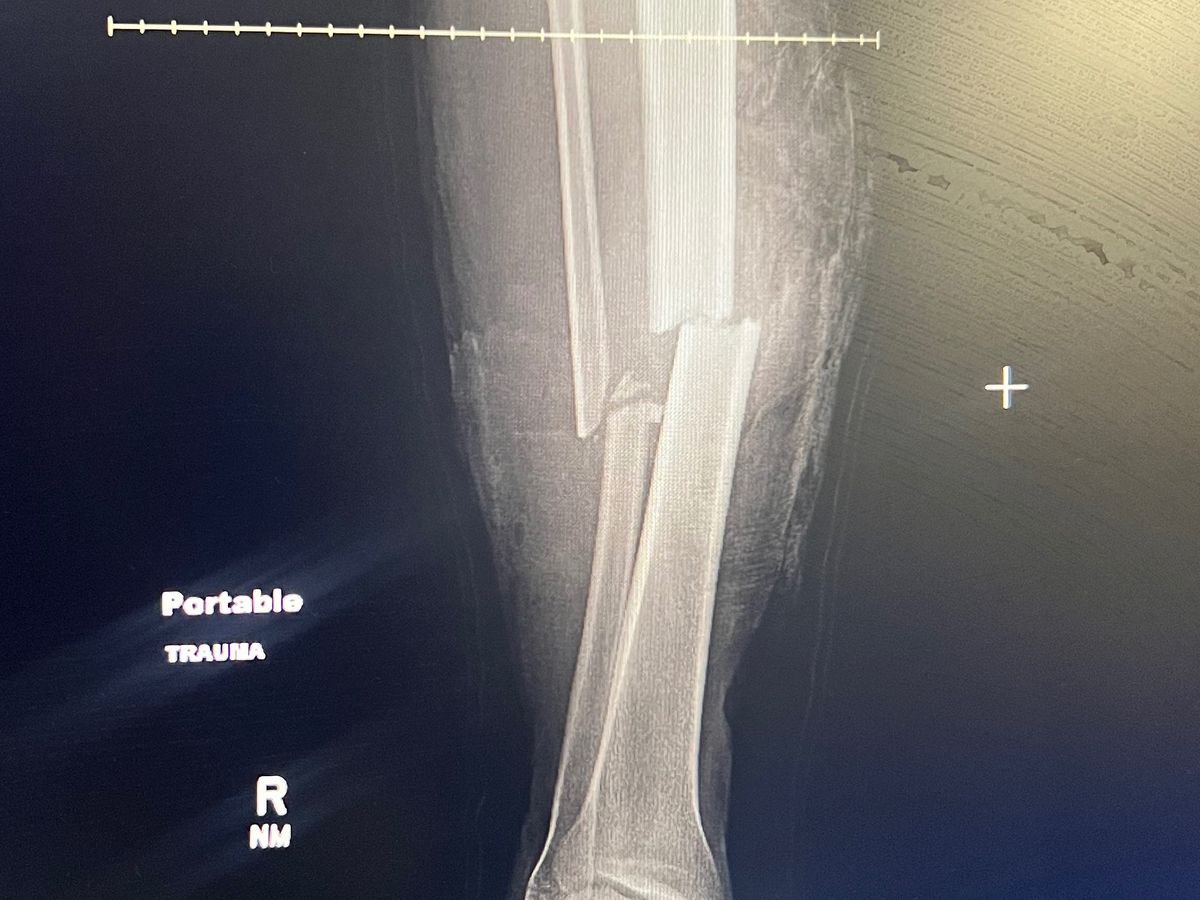

I AM HOME NOW, I GOT 6 WEEKS UNTIL I CAN WALK AGAIN. I HAD ONE OF THE BEST SURGEONS IN DFW. MY SURGERY WENT FROM 6MONTH PROCESS TO 6WEEKS. CANT WAIT TO GO BACK TO WORK.